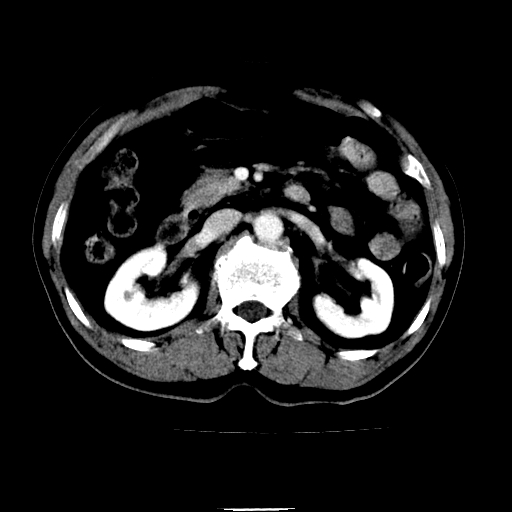

以下是引用chenqiong在2010-3-25 20:56:00的发言:[br]1、胆囊炎,胆囊息肉[br]2、肝内胆管及胆总管扩张,胆总管下端结石[br]3、十二指肠乳头旁憩室

以下是引用zxl51642在2010-3-26 10:47:00的发言:[br]胆囊炎,胆囊息肉,胆总管扩张,但未看到明显肿块,肝内胆管扩张不像恶性,炎性狭窄或阴性结石可能吧,建议mrcp,右肾小囊肿